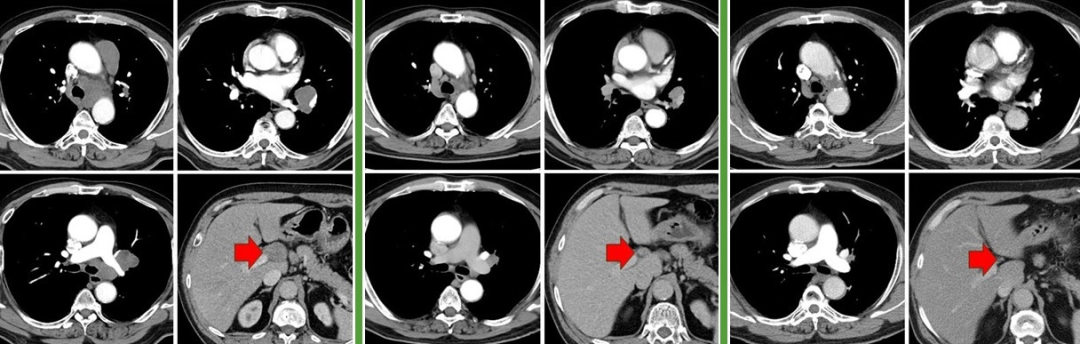

58岁,男,吸烟史40年×20支,2018.12体检发现左肺门占位,穿刺活检未见恶性成分。2019.12复查示左肺占位及纵隔淋巴较前增大,于我院行经食管超声镜下纵隔淋巴结穿刺活检,病理:小细胞癌。全身检查示左肺门、纵隔、肝门淋巴结转移,cT2bN2M1b IVA期广泛期。2020.1入组临床研究,予BGB-A317/安慰剂+EP方案化疗4周期,2020.4起行BGB-A317/安慰剂维持治疗,研究结束时揭盲,为BGB-A317组,继续免疫维持治疗至今(84周期)。截至2025.2.20

治疗小结:替雷利珠单抗+EP×4、替雷利珠单抗×84+,PFS 62个月+。

图:左起依次为基线、免疫联合化疗4周期后、末次随访